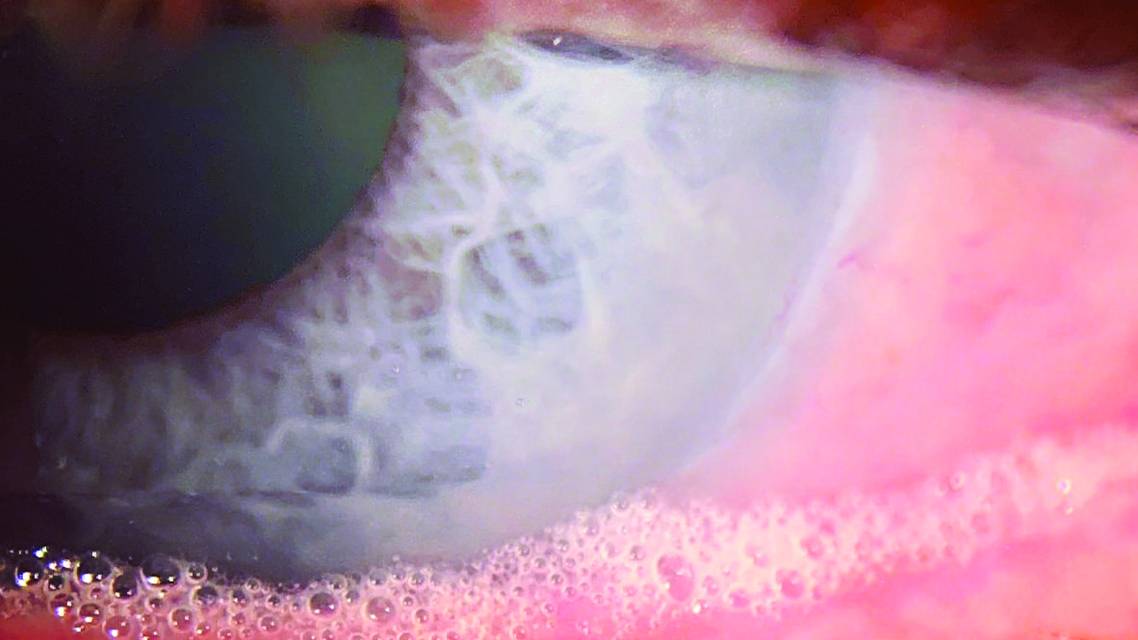

Clinically, we can see the effects of lipases on the lipids of the ocular surface. This enzymatic reaction, called saponification, appears as foamy soap bubbles (Figure) when bacterial overload and activity reaches a dysfunctional level. The true definition of saponification is the act, process, or result of making soap. This finding has been described for some time by clinicians and has been associated with blepharitis, specifically posterior blepharitis, and is better defined as meibomian gland dysfunction (MGD).2 MGD is the most common form of dry eye. Symptoms can include burning, stinging, watering, blurred vision, and a dry or gritty sensation.

In the movie Fight Club, the Paper Street Soap Company uses rendered fat and lye to make soap. Soap is an excellent cleaner because of its ability to act as an emulsifying agent. We can appreciate how dissolving and mixing oils is detrimental to ocular surface health. Bacteria are achieving a similar breakdown of lipids (using lipases instead of lye) on the ocular surface.